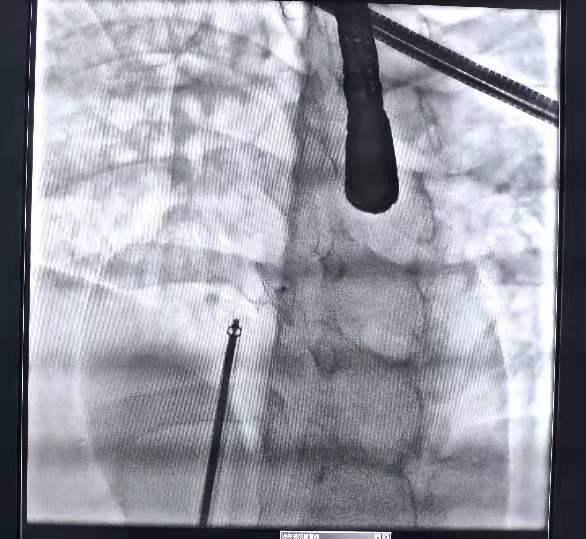

手术中,经股静脉微创置入心脏导管,将封堵器送到卵圆孔位置后,展开封堵伞,与卵圆孔完美契合,封堵住卵圆孔未闭处。

整个手术过程顺利完成,术后仅在大腿根部留有针眼大小穿刺伤口,患者预后好。